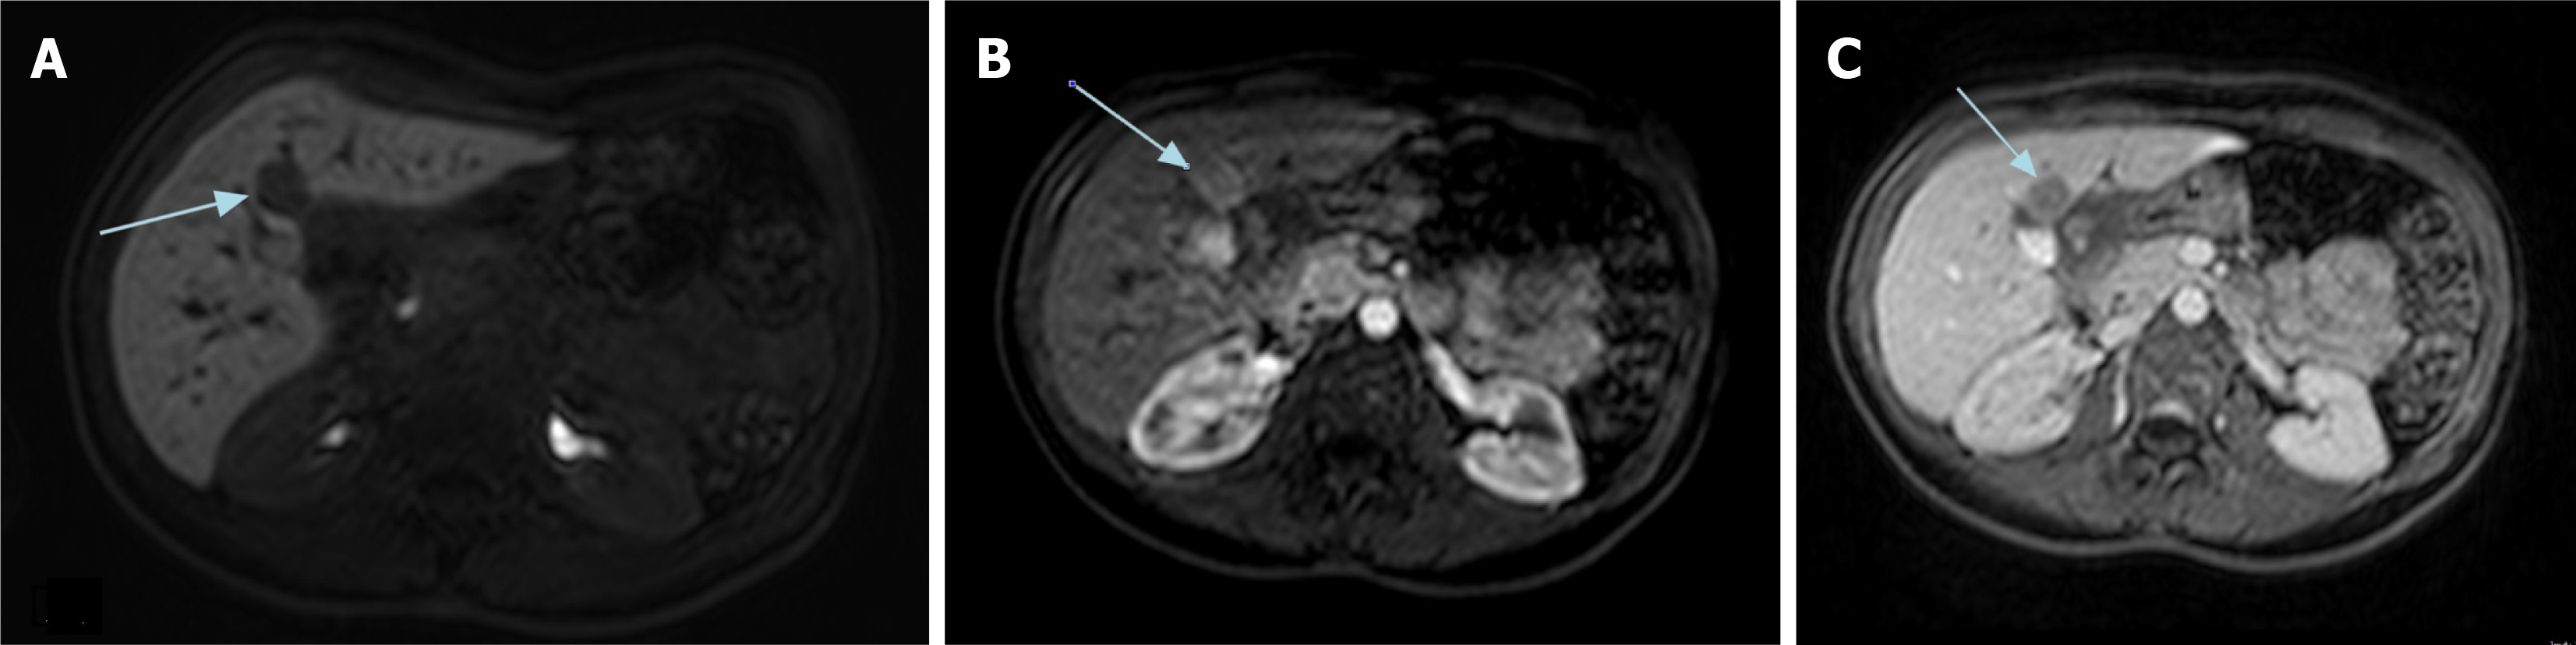

Figure 3 Abdominal magnetic resonance imaging of the hepatocellular carcinoma nodule detected in segment IV on February 2024.

A: Hepatobiliary agents; B: Wash-in phase; C: Wash-out phase.